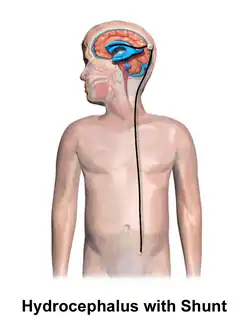

.jpg)

Hydrocephalus is treated through surgery by creating a way for the excess fluid to drain away. An external ventricular drain (EVD), also known as an extraventricular drain or ventriculostomy, provides relief in the short term.[48] In the long term, some people will need any of the various types of cerebral shunts.[48] It involves the placement of a ventricular catheter (a tube made of silastic) into the cerebral ventricles. This creates a way to bypass the flow obstruction/malfunctioning arachnoidal granulations. The excess fluid drains into other body cavities where it can be resorbed. Most shunts drain the fluid into the peritoneal cavity (ventriculoperitoneal shunt).[49] Other shunts drain the fluid into the right atrium (ventriculoatrial shunt), pleural cavity (ventriculopleural shunt), and gallbladder.[49]

A shunt system can also be placed in the lumbar space of the spine. This allows the excess fluid to be redirected to the peritoneal cavity (lumbar-peritoneal shunt).[50] Another treatment for obstructive hydrocephalus is an endoscopic third ventriculostomy (ETV). This surgery creates an opening in the floor of the third ventricle so that CSF flows directly to the basal cisterns. This treatment can shortcut any obstruction like aqueductal stenosis. This may or may not be appropriate based on individual anatomy. Some infants can be treated with ETV and choroid plexus cauterization.[51][52] Choroid plexus cauterization reduces the amount of cerebrospinal fluid produced by the brain. The technique, known as ETV/CPC, was pioneered in Uganda by neurosurgeon Benjamin Warf and is now in use in several U.S. hospitals.[51][52]